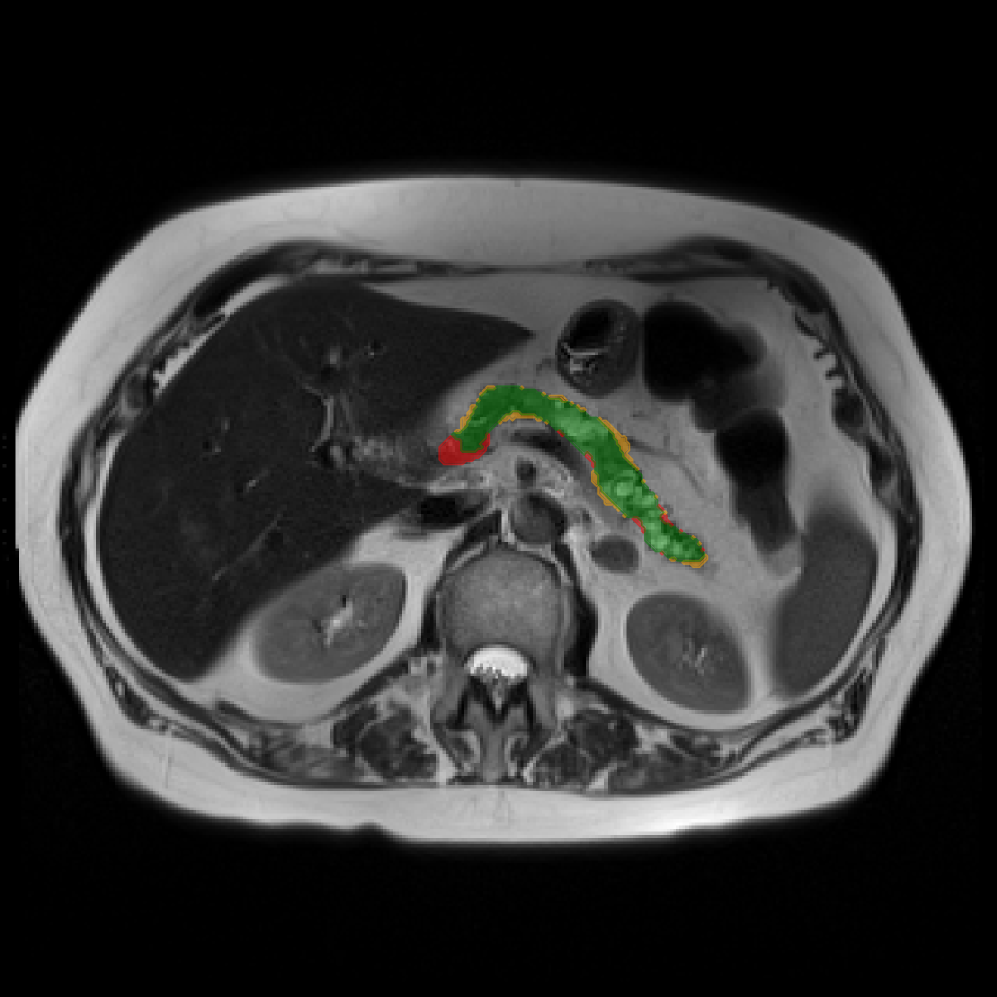

Accurate pancreas segmentation is a critical prerequisite for precise cyst analysis and classification. Recently, we developed PanSegNet [zhang2025large], a novel segmentation architecture incorporating linear self-attention layers [zhang2022dynamic] within the nnUNet framework [isensee2021nnu] to enhance global information modeling capabilities while maintaining computational efficiency (Fig. 1). PanSegNet demonstrated exceptional segmentation performance across both T1W and T2W modalities, achieving mean dice scores of 86.817.30% and 89.626.38%, respectively (Table 1, Fig. 2b-c). This performance significantly exceeded that of Swin-UNETR [hatamizadeh2021swin], one of the most used state-of-the-art transformer-based medical segmentation models, which achieved dice scores of 79.091.40% and 76.290.66% for T1W and T2W, respectively (). In this study, we integrated PanSegNet into our Cyst-X engine along with a classifier for risk prediction. In Section 2.2, we show that the choice of segmentation model affects the classification results. The performance advantage of PanSegNet was consistent across all seven medical centers, demonstrating robust generalization despite variations in imaging protocols and equipment (Table 1). This cross-institutional reliability is particularly important for clinical applications, where model performance must remain consistent regardless of imaging site or acquisition parameters.

Each patient was categorized into one of these three ground truth classes: no risk/control, IPMN low-risk, or IPMN high-risk. To evaluate variability in image acquisition, we applied uniform manifold approximation and projection (UMAP) to image quality indicators, revealing distinct clustering patterns by imaging center and slice thickness. This heterogeneity reflects real-world clinical variability, enhancing the dataset’s generalizability while presenting technical challenges for model development. Fig. 6 shows examples of low-grade, high-grade, and cancer developing IPMNs from the Cyst-X dataset.